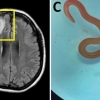

호주 건망증 여성 뇌 속에 8㎝ 벌레 살아서 ‘꿈틀’…

비단뱀 기생 회충…“인체내 발견은 최초 보고사례”야생풀 섭취 이력…사람·짐승 공유지의 위험성 재확인 건망증과 우울증을 앓던 64세 호주 여…